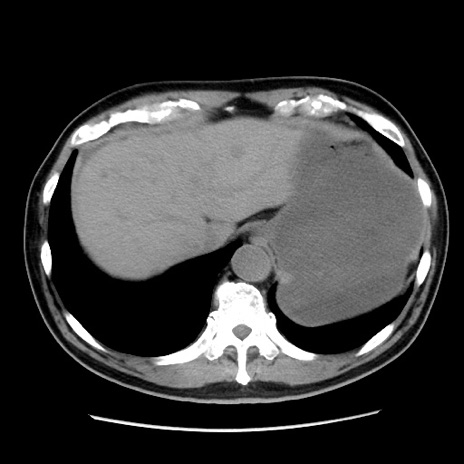

冠状断像